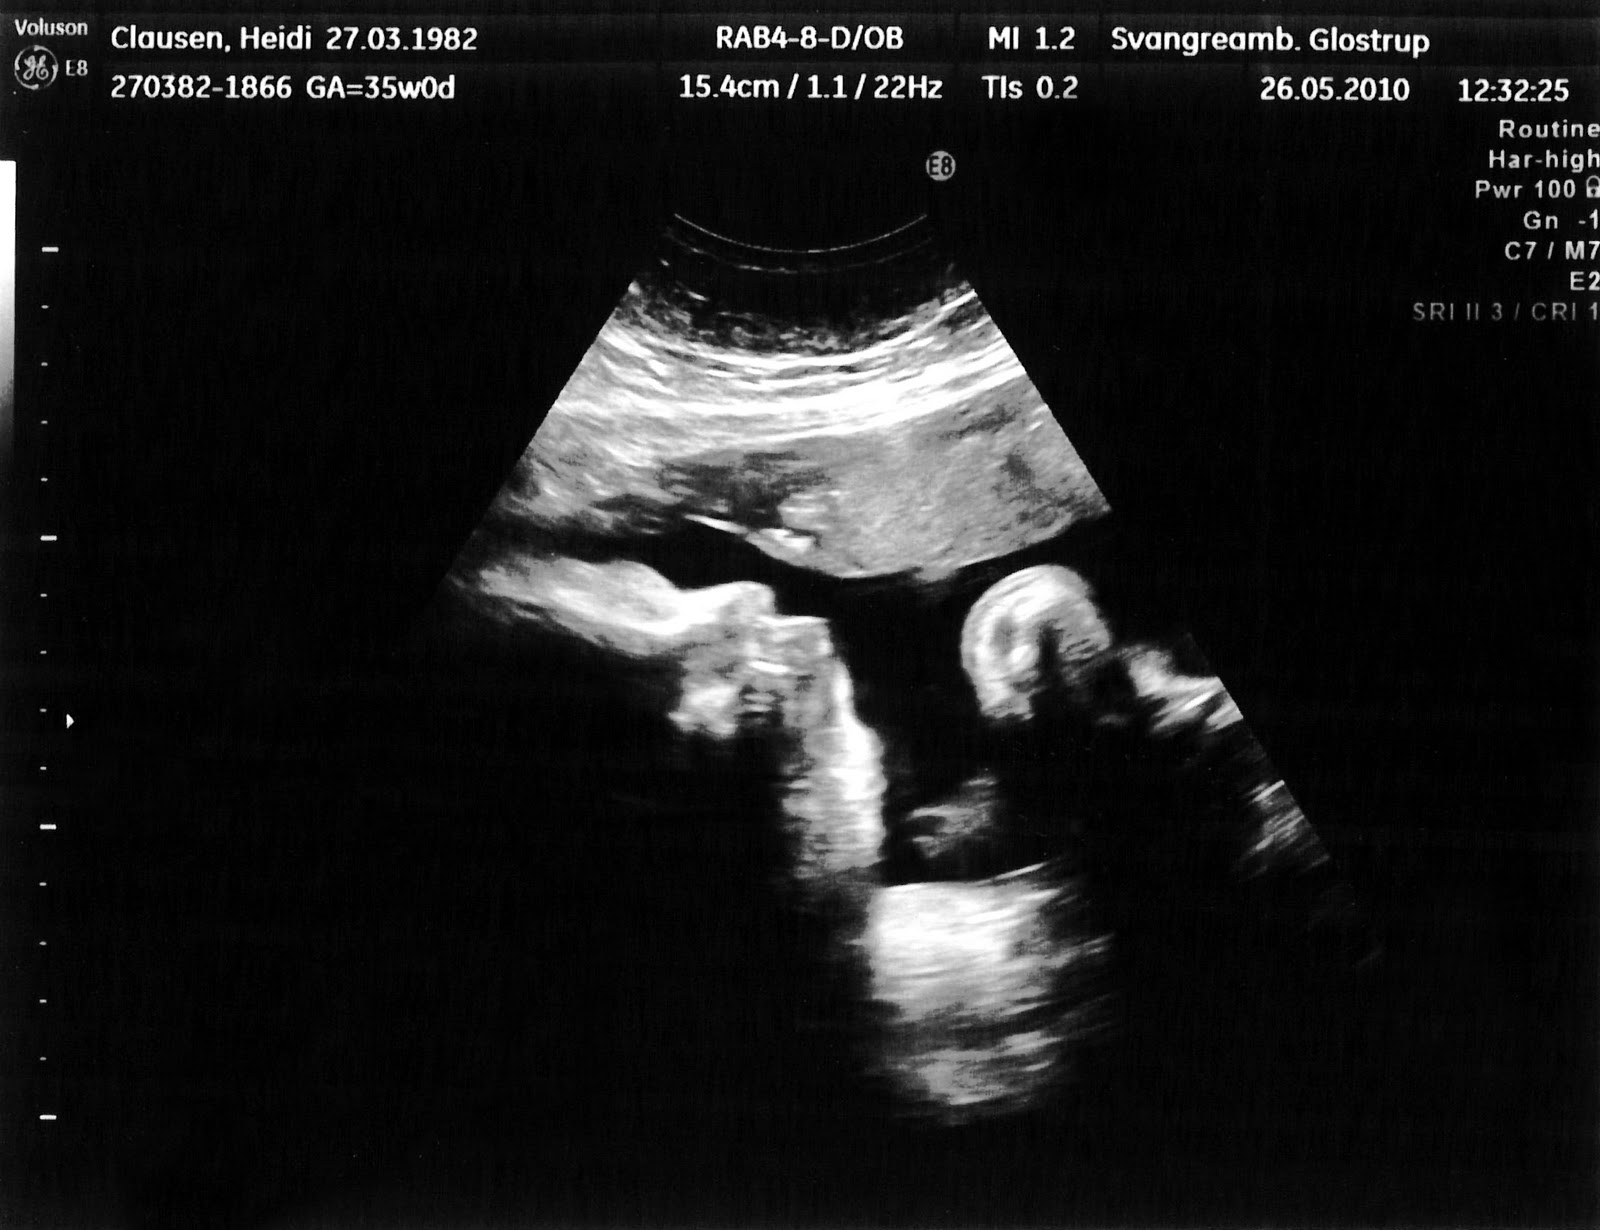

I dag har jeg været til min sidste skanning og alt var lige som det skulle være, i dag vejer han 2427 g, det er lige som det skal være.

I dag var jeg også rigtig heldig, han lå bare helt rigtig og jeg har fået 2 rigtig fine 3D billeder af ham, han er bare så dejlig, nu blev det hele lige lidt mere virkeligt for nu har man jo hele tiden et billede inde i hovedet af ham, jeg glæder mig bare så meget til han kommer ud til os.